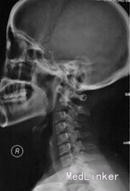

外院颈椎X线片检查显示颈椎退行性改变、颈椎不稳,双侧臂丛B超检查显示左侧锁骨下动脉在锁骨上凹处将神经股部完全隔离成两部分,右侧神经股部的分布也与正常有异,肌电图检查提示双上肢慢性神经源性损伤电生理表现,主要累及C8-T1神经,不排除臂丛下干损伤可能,遂诊断为双侧胸廓出口综合征,建议手术治疗,但患者未接受手术治疗。 2个半月后患者来我院就诊,颈椎CT检查显示C3-4、C5-6、C6-7椎间盘突出、颈椎退行性变,诊断为“双侧胸廓出口综合征、颈椎退行性变”,建议手术治疗。 3个半月后患者入院,查体示C5-6、C6-7棘突及左侧棘旁压痛,双侧胸锁乳突肌及颈外静脉交叉点压痛(以左侧为重),左肩胛内上角压痛,左前臂内侧感觉及左手感觉减退,痛温觉减退;双肩外展肌肌力Ⅴ级,双侧肱二头肌、肱三头肌肌力Ⅴ级,双手握力减退(以左手为重)。